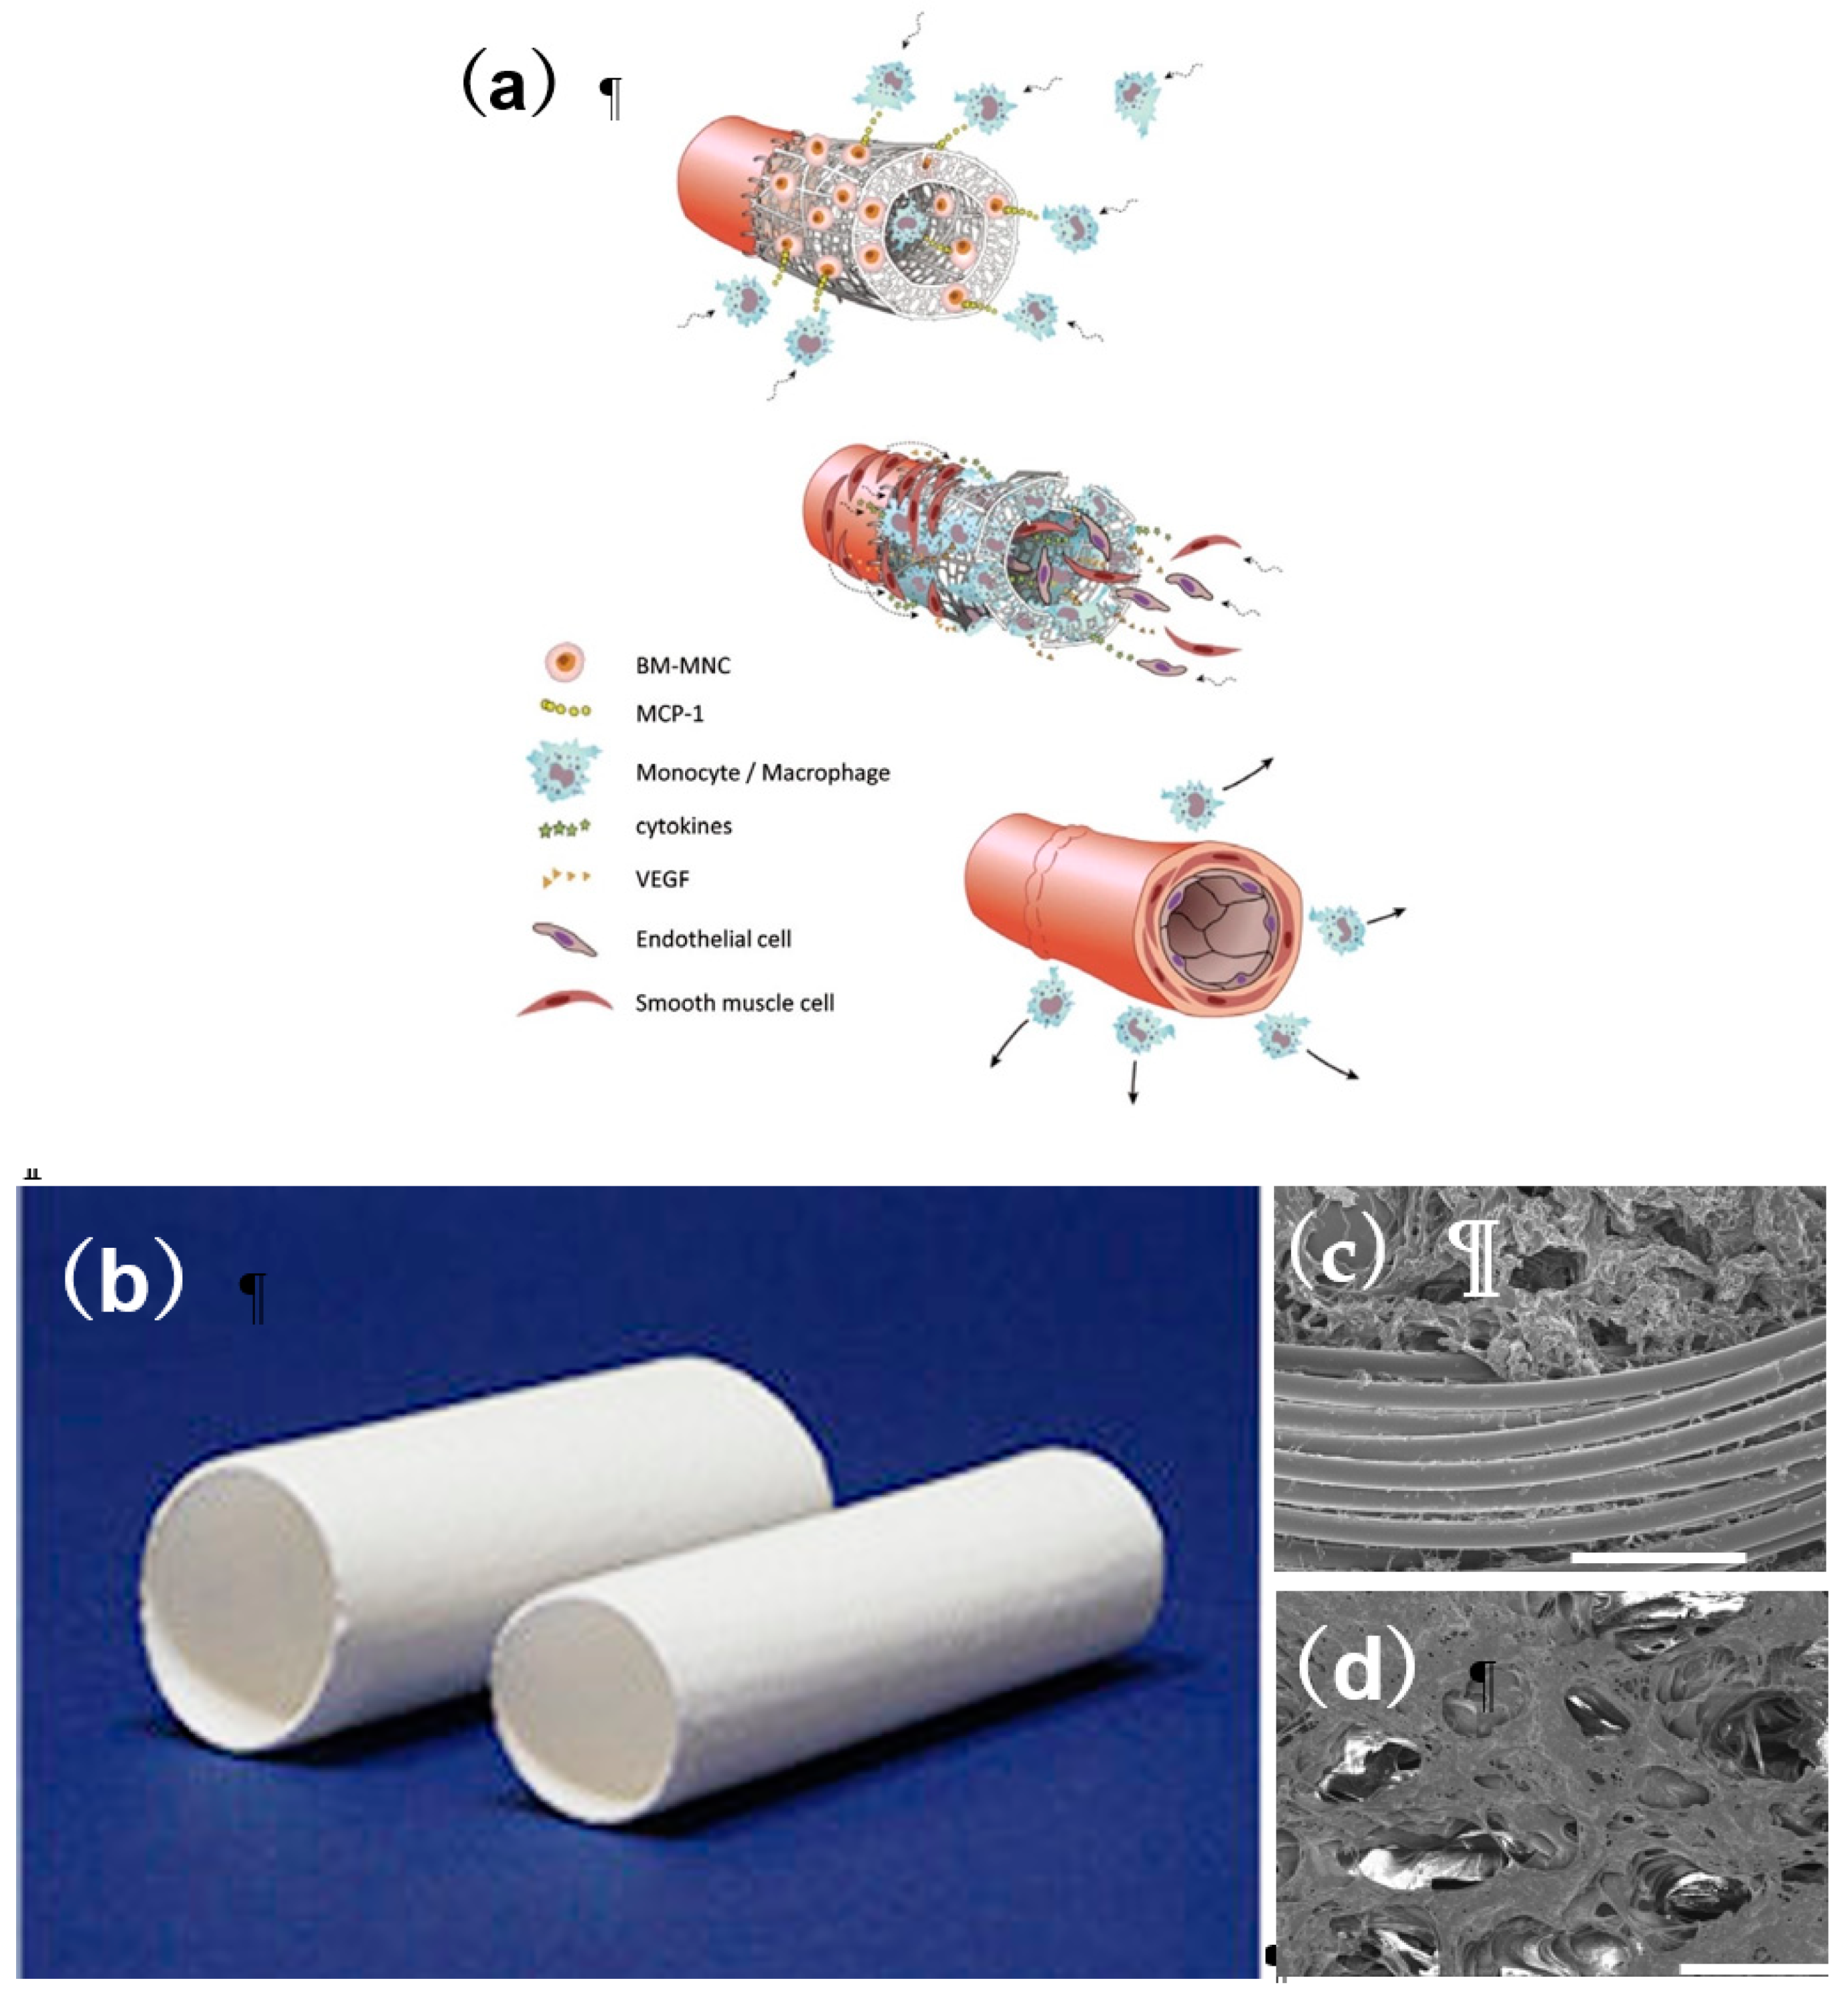

2.3. Application of Cell Biology to TEVG

3. Clinical Study in Venous Model

- Shinoka, T.; Matsumura, G.; Hibino, N.; Naito, Y.; Watanabe, W.; Konuma, T.; Sakamoto, T.; Nagatsu, M.; Kurosawa, H. Midterm clinical result of tissue-engineered vascular autografts seeded with autologous bone marrow cells. J. Thorac. Cardiovasc. Surg. 2005, 129, 1330–1338. [Google Scholar] [CrossRef] [PubMed] [Green Version]

- Hibino, N.; McGillicuddy, E.; Matsumura, G.; Ichihara, Y.; Naito, Y.; Breuer, C.K.; Shinoka, T. Late-term results of tissue- engineered vascular grafts in humans. J. Thorac. Cardiovasc. Surg. 2010, 139, 431–436. [Google Scholar] [CrossRef] [PubMed]

- Harrington, J.K.; Chahboune, H.; Criscione, J.M.; Li, A.Y.; Hibino, N.; Yi, T.; Villalona, G.A.; Kobsa, S.; Meijas, D.; Duncan, D.R.; et al. Determining the fate of seeded cells in venous tissue-engineered vascular grafts using serial MRI. FASEB J. 2011, 25, 4150–4161. [Google Scholar] [CrossRef] [Green Version]

- Hibino, N.; Yi, T.; Duncan, D.R.; Dean, E.; Naito, Y.; Dardik, A.; Kyriakides, T.; Madri, J.; Pober, J.S.; Shinoka, T.; Breuer, C.K. A critical role for macrophages in neovessel formation and the development of stenosis in tissue-engineered vascular grafts. FASEB J. 2011, 25, 4253–4263. [Google Scholar] [CrossRef] [PubMed] [Green Version]